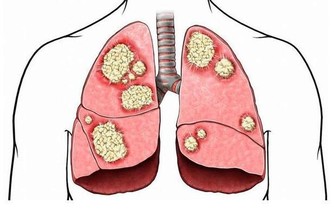

大蒜被譽為「天然的廣譜抗生素」,對多種球菌、桿菌(痢疾桿菌、傷寒桿菌、百日咳桿菌、大腸埃希菌)、病毒、真菌、阿米巴原蟲、陰道滴蟲、蟯蟲等,均有抑制或殺滅的作用。大蒜中還含有一種辛辣、含硫的揮發性植物殺菌素——大蒜素(抑制腫瘤細胞生長,抗癌),其對高血糖(預防糖尿病)、高血壓等心血管疾病(抗血栓、降血脂、降血壓)人群非常有幫助。另外,民間也有用大蒜預防和治療百日咳、細菌性痢疾、流行性感冒等疾病的驗方。而被譽為「印度醫學之父」的查拉克也曾說過:「大蒜除了討厭的氣味外,實際價值比黃金還高。」